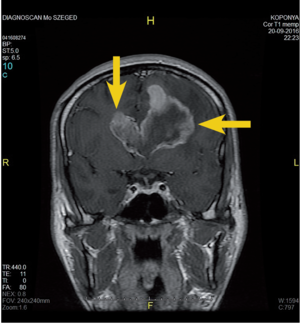

3.6.2. Daganatok: az agy (64–72. ábra)

- MRI: T2, FLAIR, T1/T1gad, DWI.